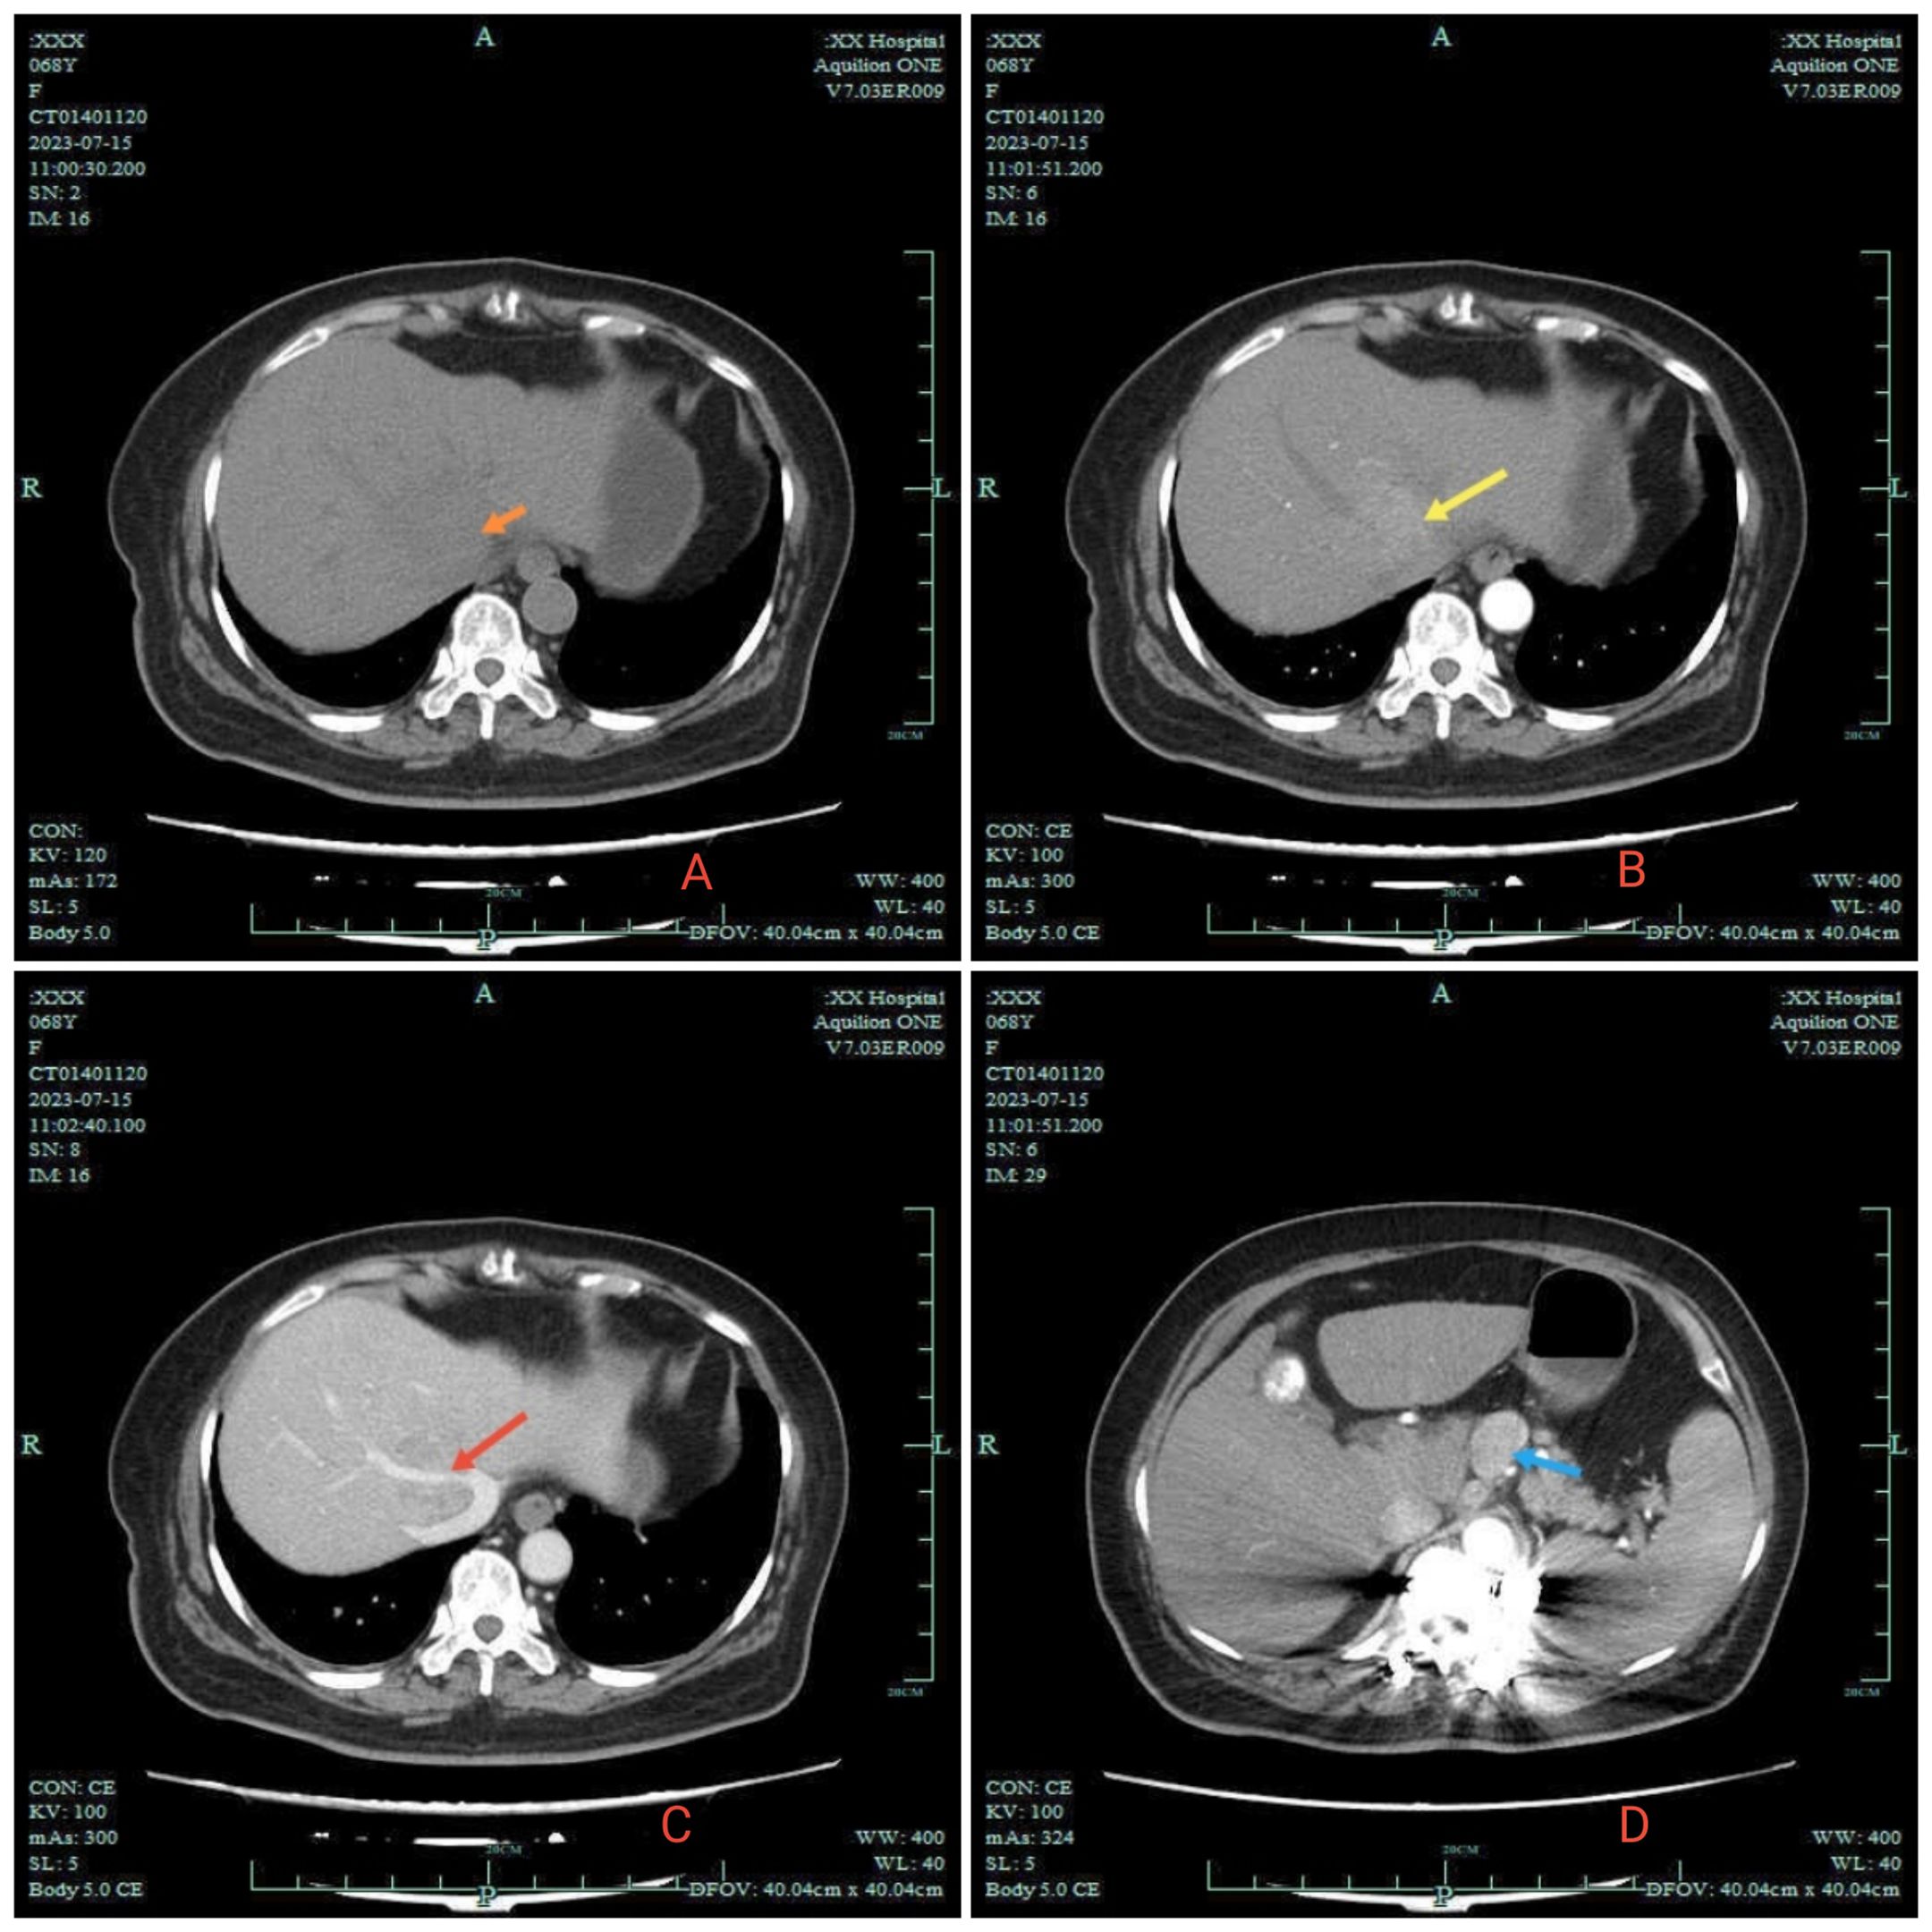

This report presents the case of a 70-year-old female patient with hepatocellular carcinoma (HCC) who was hospitalized for fever of unknown origin.We confirmed the diagnosis of HCC with lymphadenopathy through needle biopsy. The patient experienced hypertension and malaise after therapy with tislelizumab plus lenvatinib. Additionally, there was a persistent decrease in T3 and T4 levels accompanied by elevated TSH levels. During treatment, tumor regression and notable shrinkage of enlarged lymph nodes met the criteria for surgical intervention. However, since the patient's family declined surgery, the tumor subsequently progressed, resulting in clinical deterioration. This case highlights the uncommon occurrence of hypothyroidism after targeted immunotherapy in HCC patients and emphasizes the critical role of monitoring thyroid function in prognosis assessment. Conclusion: Hypothyroidism following combination therapy with tislelizumab and lenvatinib in HCC may indicate a favorable therapeutic response. Early surgical intervention is recommended once tumor shrinkage and symptom improvement occur.